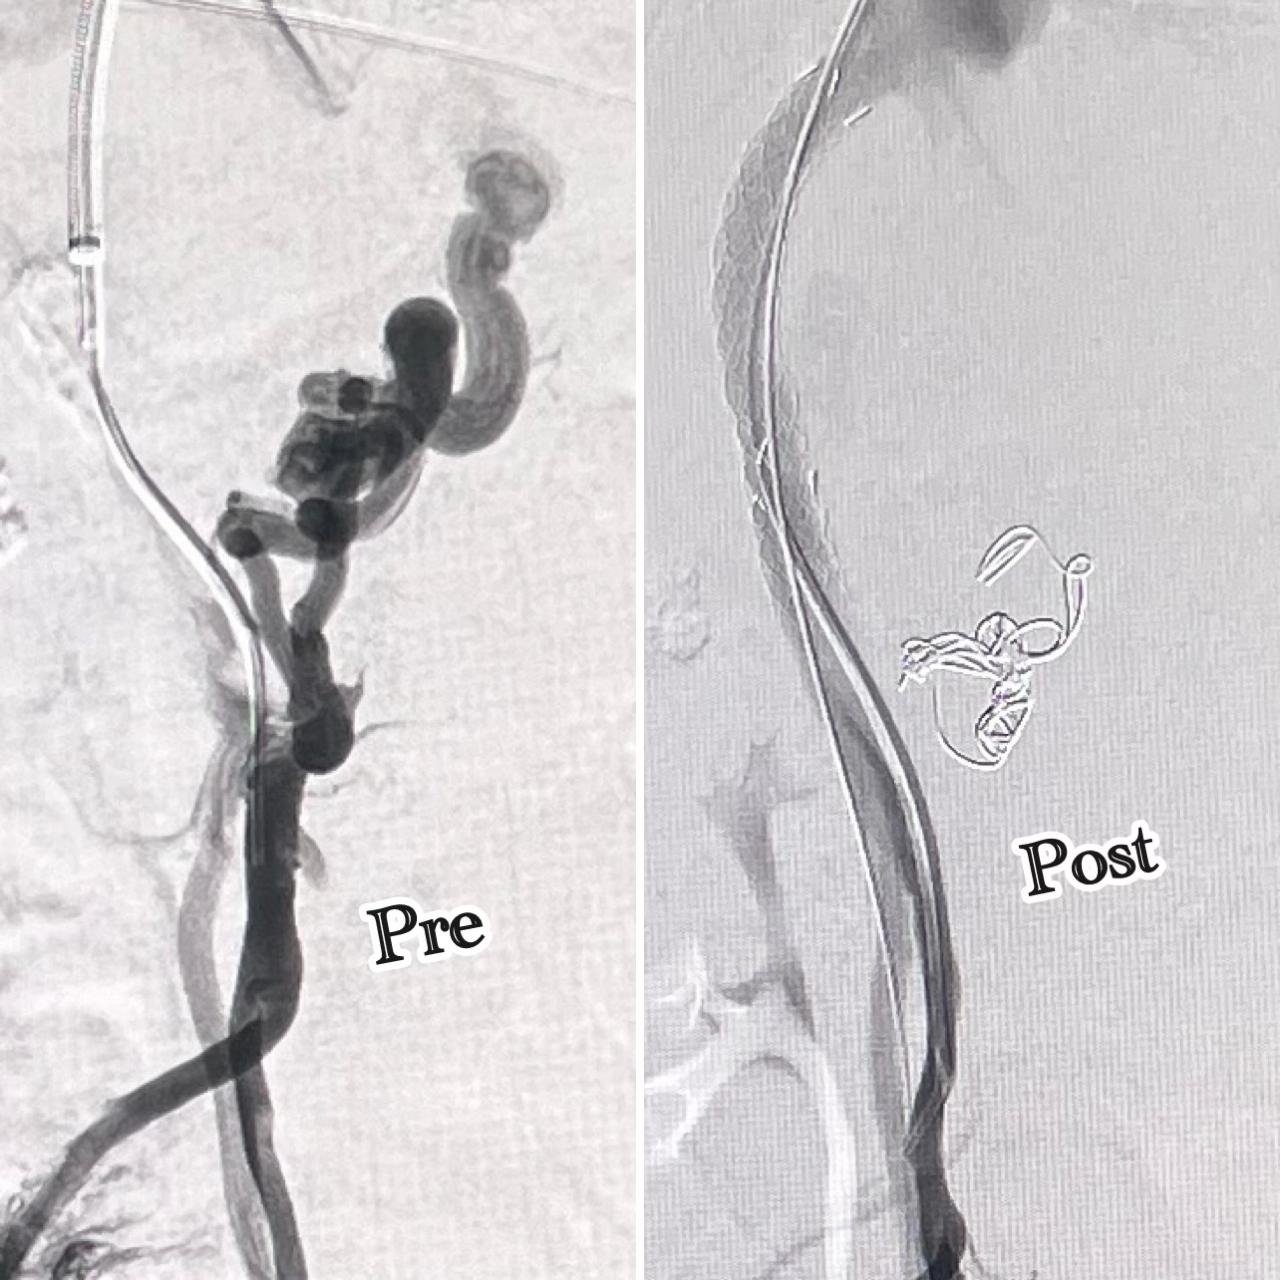

Vascular Interventions: Uterine Fibroid Embolization, Prostatic Artery Embolization, GI Bleed Embolization

Neurovascular & Other Procedures: Osteoid Osteoma Ablations, Neurovascular Interventions